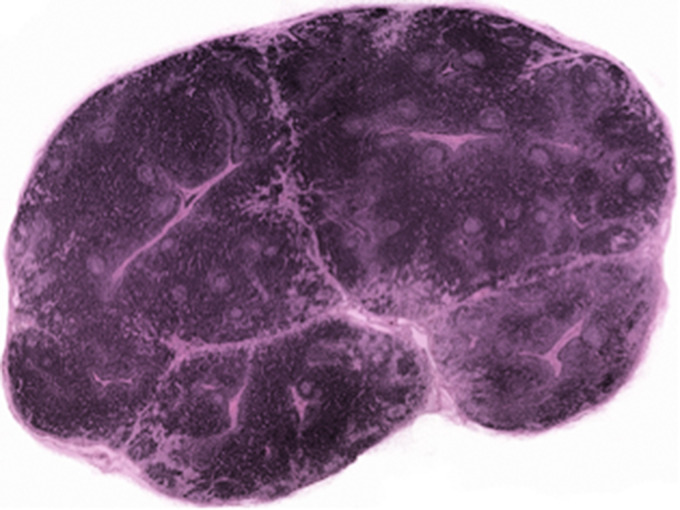

Abstract Image